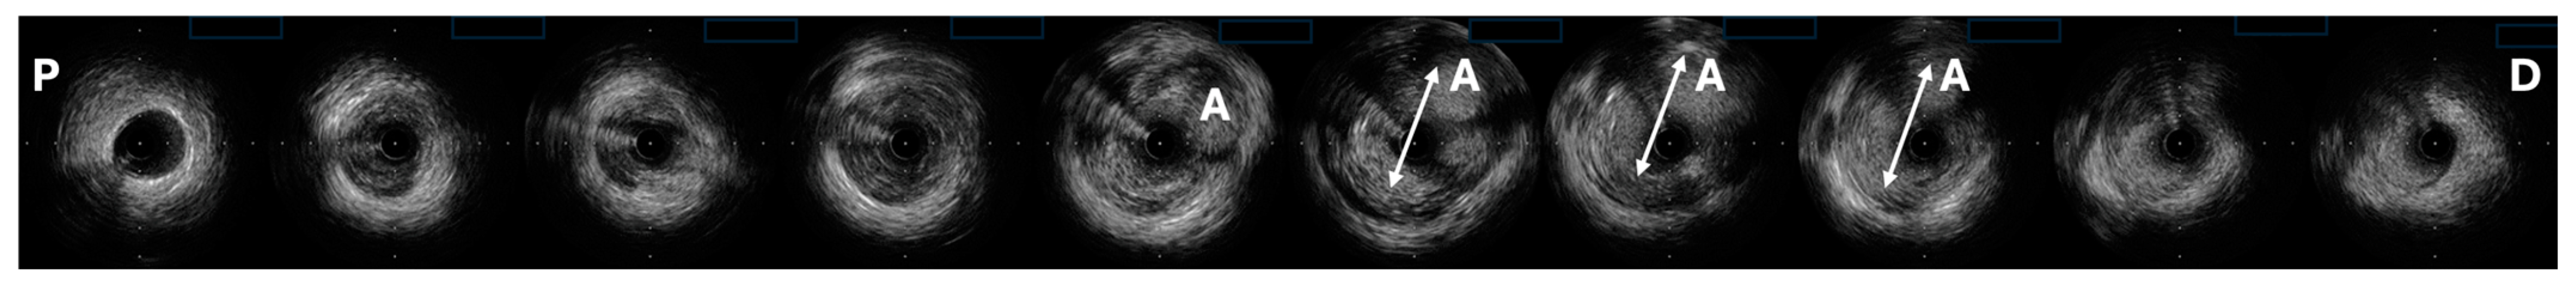

- Fathelbab, H.; Freire, S.J.C.; Jiménez, J.L.; Piris, R.C.; Menchero, A.E.G.; Garrido, J.R.; Fernández, J.F.D. Detection of spontaneous coronary artery spasm with optical coherence tomography in a patient with acute coronary syndrome. Cardiovasc. Revascularization Med. 2017, 18, 7–9. [Google Scholar] [CrossRef]